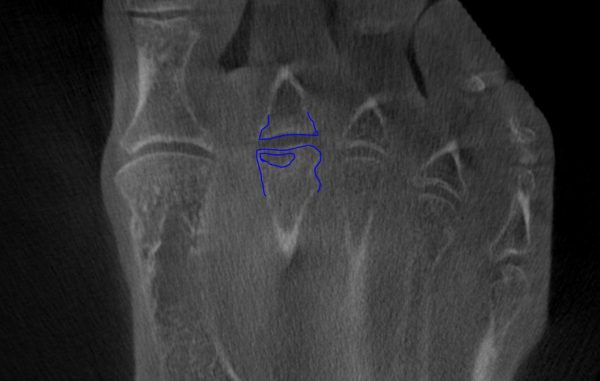

Home Schwerpunkte Krankheitsbilder Morbus Köhler 1 & 2 Morbus Koehler 2 DVT tranversal mit blau gezeichnetem Köpfchen

Morbus Koehler 2 DVT tranversal mit blau gezeichnetem Köpfchen